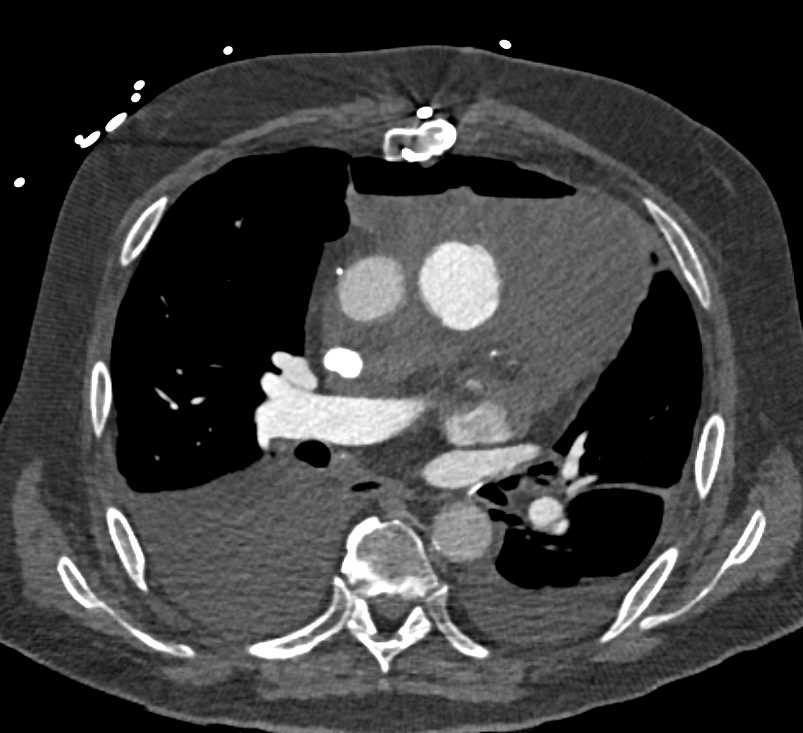

Diagnosis

Post Cardiac Surgery Changes